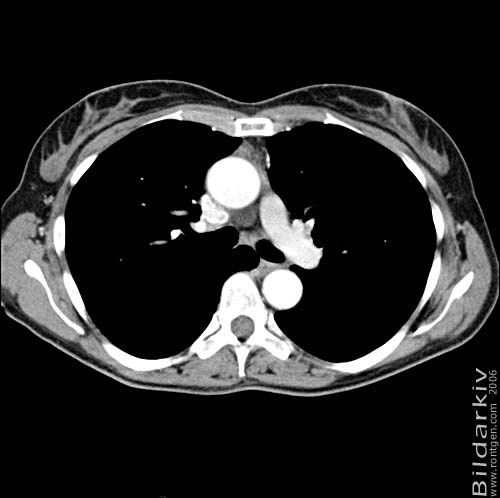

Thorax 25

Snitt över thorax med kontrast. Sk. mediastinum-fönstersättning.

CT Röntgen Helsingborgs lasarett

Mediastinum